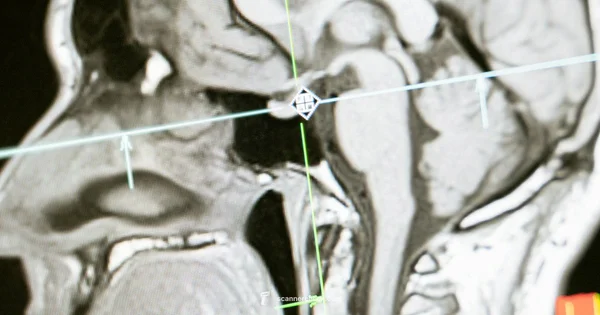

Magnetism and radio waves: An MRI machine generates a strong magnetic field that aligns hydrogen atoms in your body's water molecules. When a radiofrequency pulse is applied, those atoms emit signals that a computer converts into images. The result is cross sectional slices of the brain that look at different tissues, fluids, and pathways. Different sequences emphasize various properties, so radiologists can distinguish gray matter, white matter, cerebrospinal fluid, and abnormal tissue. MRI does not use ionizing radiation, which makes it a preferred option for many brain investigations. The exact sequences and whether a contrast agent is used depend on the clinical question and patient factors. With newer high field scanners, such as 3T systems, image detail improves further, aiding in detecting small lesions. The goal is a precise map of anatomy and pathology that can guide management.